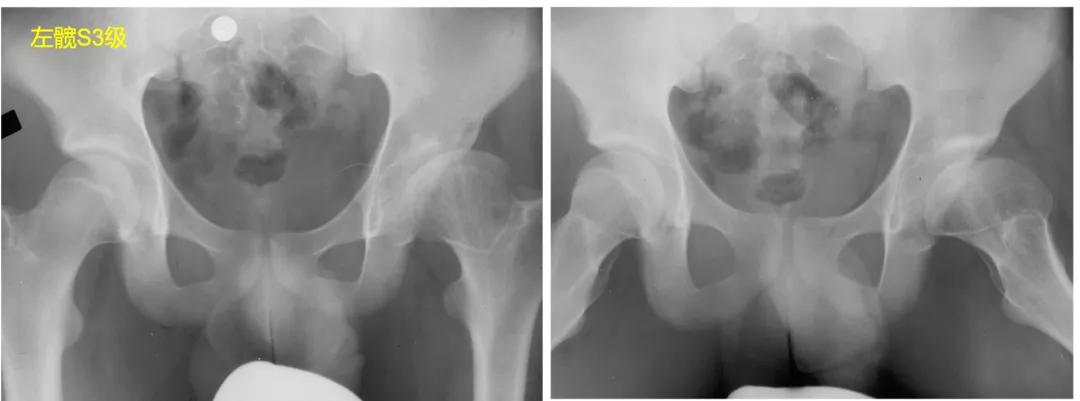

S3:股骨头呈卵圆形,在正位片或蛙式位片上,股骨头不圆>2mm。

S4:股骨头扁平,在正位片或蛙式位片上,股骨头负重区扁平>1cm,髋臼也呈扁平状,畸形匹配。